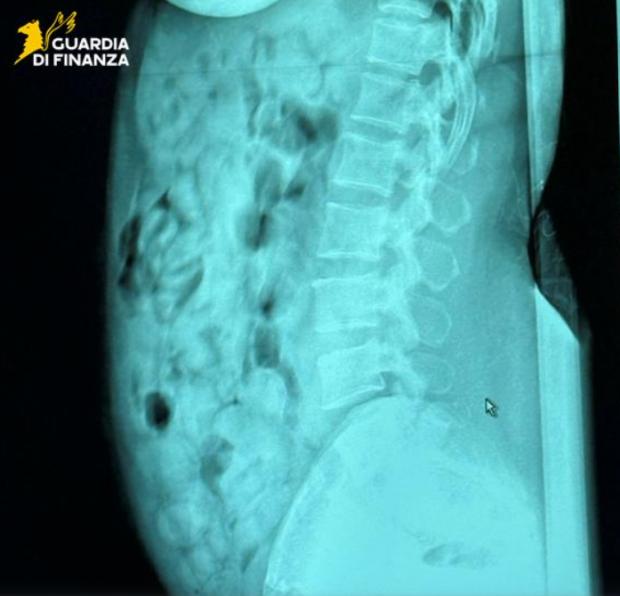

Ulterior, radiografiile efectuate au confirmat prezența în stomacul femeii a 120 de capsule de plastic, învelite în mai multe straturi de bandă adezivă, relatează Il Messaggero.